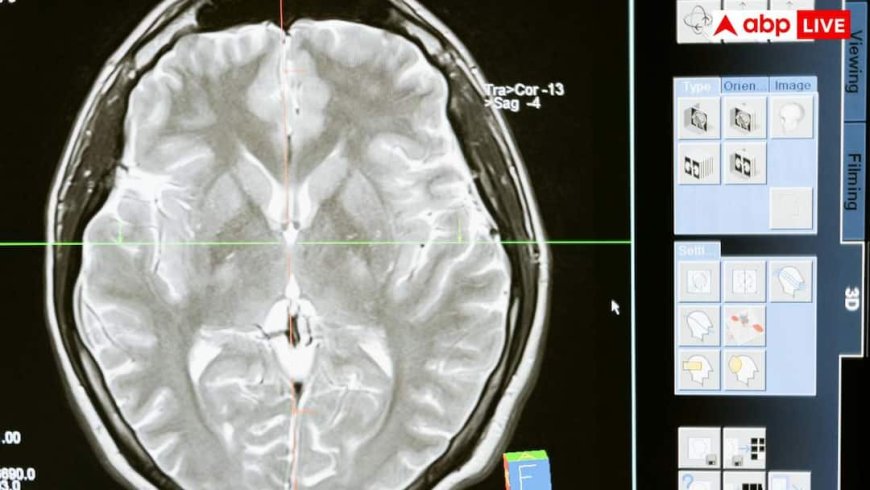

न्यूरोलॉजिस्ट की मानें, तो जब बच्चों में दौरे पड़ने के कारणों की जांच की गई और उनके दिमाग का स्कैन किया गया, तो दौरे पड़ने की मुख्य वजह पैरासाइटिक इंफेक्शन या दिमाग में मौजूद कीड़े पाए गए. इसके बारे में जानना हर किसी के लिए जरूरी है कि कैसे पैरासाइटिक इंफेक्शन बच्चों में दौरे पड़ने का मुख्य कारण बन रहा है.

दिमाग में पैरासाइटिक इंफेक्शन की मुख्य वजह न्यूरोसिस्टिकोसिस नाम की स्थिति है. यह एक ऐसी स्थिति है, जिसमें हमारे दिमाग में सूअर के फीताकृमि, जिन्हें हम पोर्क टैपवार्म भी कहते हैं, उनके अंडों के कारण यह समस्या होती है. ये अंडे कहीं भी हो सकते हैं, जैसे मिट्टी में, गंदे खाने में या किसी पत्तेदार सब्जियों के बीच में. इनके सेवन से ये अंडे हमारे खून के माध्यम से सीधे दिमाग में चले जाते हैं और वहां जम जाते हैं. ध्यान देने वाली बात यह है कि ये कीड़े नहीं होते, बल्कि उनके अंडे होते हैं.

न्यूरोसिस्टिकोसिस में दौरे पड़ने का सबसे बड़ा कारण यह है कि दिमाग इन अंडों से बचने के लिए कई तरह की प्रतिक्रिया करता है. जब ये अंडे दिमाग में पहुंच जाते हैं, तो हमारा शरीर उनके चारों तरफ सूजन पैदा कर देता है, ताकि बाहरी खतरों को एक जगह रोका जा सके. इसी सूजन की वजह से हमारे दिमाग की कोशिकाओं के बिजली के सिग्नल यानी इलेक्ट्रिकल सिग्नल में गड़बड़ी पैदा हो जाती है, जो दौरे पड़ने का कारण बनती है. जैसे-जैसे यह अंडा दिमाग में सड़ना शुरू करता है, वैसे-वैसे कई तरह की दिक्कतें होने लगती हैं, जिनमें सिरदर्द और दौरे पड़ना शामिल है.